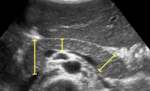

معنی دیامتر در سونوگرافی چیست

دیامتر که در معنی لغوی به معنای قطر یا ضخامت است. منظور از دیامتر در سونوگرافی اندازه ضخامت یا قطر هر اندامی است که در تشخیص سونوگرافی برای سلامت یا بیماری، مورد بررسی قرار گیرد. مثلا معنای دیامتر در بارداری میتواند ضخامت کیسه حاملگی (Sac) باشد.

اندازه طبیعی دیامتر کبد

پزشکان از روش سونوگرافی برای تعیین اندازه یا دیامتر کبد استفاده می شود به این دلیل که وقتی کبد بیش از حد بزرگ شده باشد، پزشک متخصص می تواند این بزرگ شدن را روی اشعه ایکس تشخیص دهد. میانگین اندازه طبیعی دیامتر کبد در بزرگسالان 14 سانتی متر است که اگر اندازه کبد از حد طبیعی بیشتر باشد می تواند نشانگر بیماری های جدی کبدی باشد.